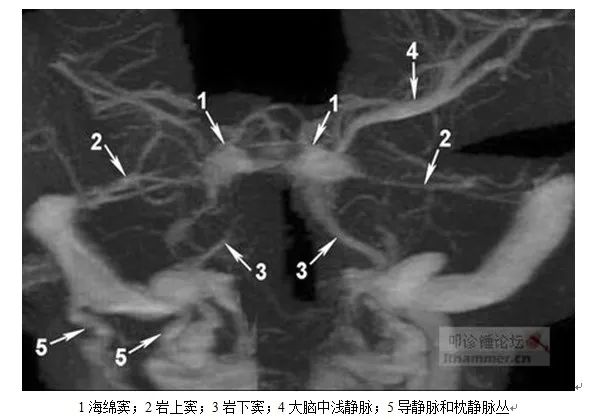

硬脑膜内外层之间形成腔隙,为颅内静脉血的血流通道,称为硬脑膜窦,分为后上组和前下组(窦壁内面衬有内皮细胞,无静脉瓣,无平滑肌及外膜,故无收缩性易破裂出血)。

1.海绵窦、海绵间窦:蝶鞍两侧两侧硬脑膜内,多发结缔组织形成多个小腔,呈海绵状。左右海绵窦之间,鞍膈前后附着缘,前面为海绵间前窦,后面为海绵间后窦,连同左右海绵窦,环绕垂体形成环窦。此外,在蝶鞍底部还有海绵间下窦,位于垂体下面多呈裂隙状,回流垂体静脉(海绵间下窦大小对经鼻垂体腔镜术时非常重要)。

2.岩上窦:位于小脑幕附着于颞骨岩部上缘的沟内,前通海绵窦,后通横窦。收集小脑静脉、大脑下静脉和鼓室静脉,与岩下窦和基底静脉丛交通。

3.岩下窦:位于颞骨岩部后面下缘的岩枕裂内,前通海绵窦后下,后通颈静脉上球或乙状窦,收集蜗小管和前庭小管的迷路静脉和来自脑桥、延髓和小脑下面的属支。